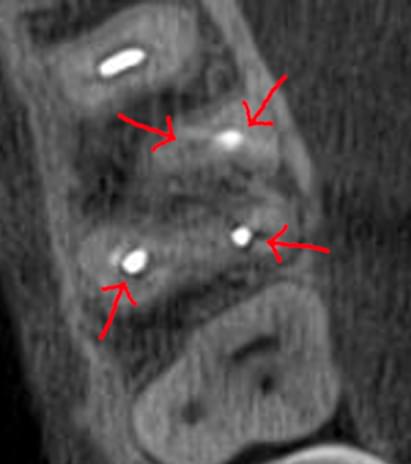

Часто причиною зубного болю є гайморит, і навпаки — причиною запалення пазух є хворий зуб. На звичайному знімку пазуха виглядає як темна пляма. На КТ ми бачимо стан слизової, наявність кіст або сторонніх тіл (наприклад, залишків пломбувального матеріалу), що критично важливо для правильного діагнозу.